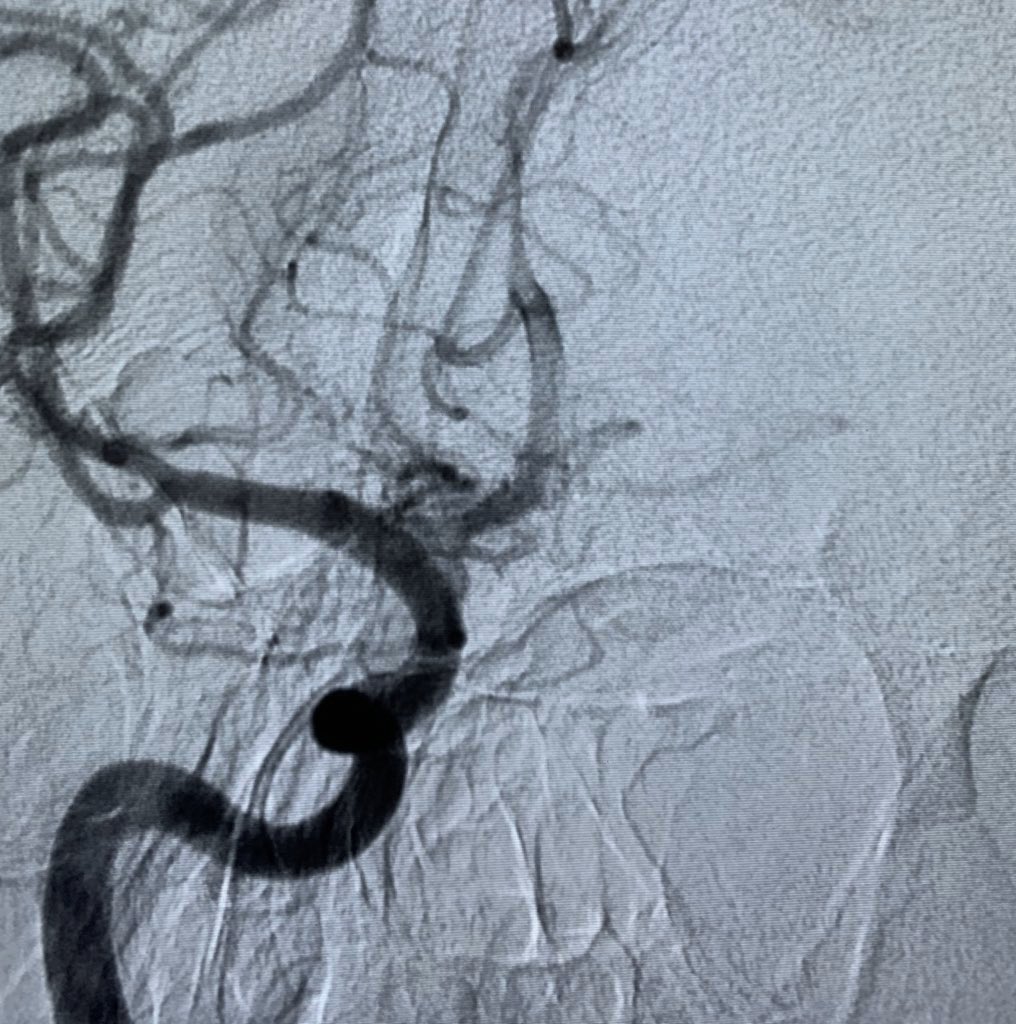

A quick case on Monday morning. Thrombus in the transition zone between M1 and M2.

#ADAPT with Sofia 5 FR.#thrombectomy@YoungNIR@LINNConline@ESOstrokepic.twitter.com/1nx2Bn3gX4